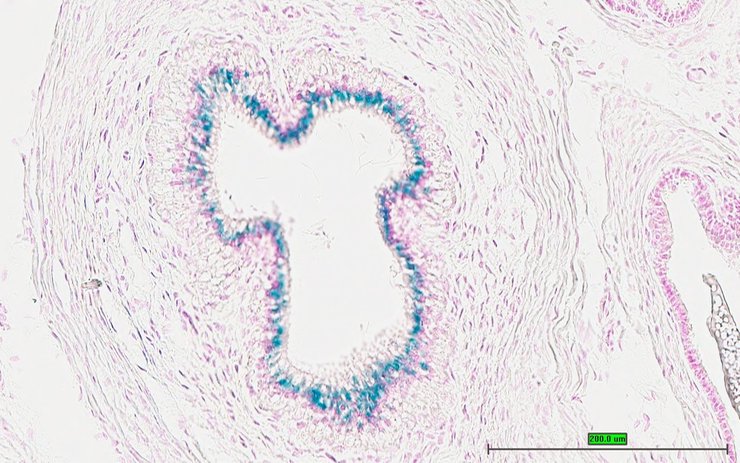

TS28: epididymis Present UC Davis_1872645

Specimen UC Davis_1872646: postnatal adult; Cd200r4tm1.1(KOMP)Wtsi/Cd200r4+ (more )

Structure Level Pattern Image Note

TS28: ductus deferens Present UC Davis_1872646 vas deferens